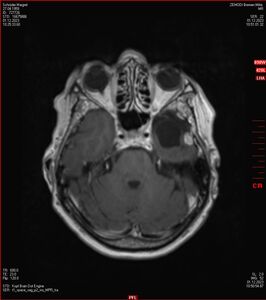

Die letzten drei Bilder Zeigen aus meiner Sicht den Tumor, der im Jahr 2021 bestrahlt wurde.

Zum Vergleich nun auch die Bilder vom 1.12.2023:

Ich denke, in den letzen 12 Monaten sind da ein paar Rezidive gewachsen,  vor 12 Monaten waren sie auch schon zu erkennen - vorher noch nicht. Nun hoffe ich auf den Rat des Spezialisten. Hoffendlich kann man etwas machen.